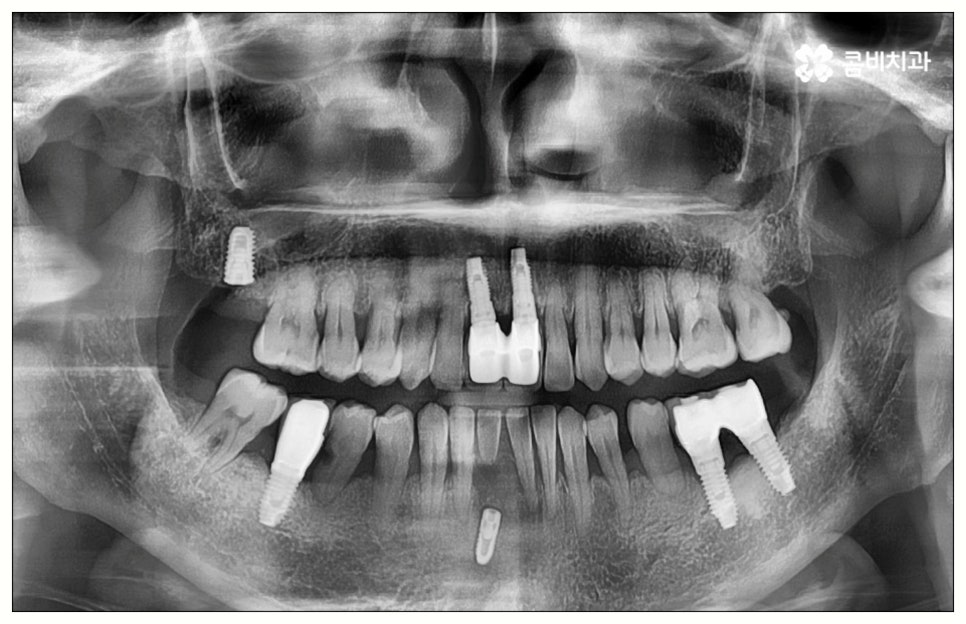

특히 임플란트 기술의 꽃이라고 할 수 있는 원데이임플란트 방식을 이용하면 발치부터 식립, 임시치아 장착까지 하루 만에 가능하기 때문에 비교적 긴 치료 기간이나 잦은 내원에 따른 어려움, 통증에 대한 두려움 등 환자분들이 느끼는 여러가지 부담을 많이 줄여줄 수 있어요. 치아 상실과 동시에 원데이임플란트 시술을 받으면 치아 공백 기간을 줄여 치조골이 위축되는 것을 방지해 주어 뼈 보존 측면에서도 유리하며, 특히 앞니와 같이 입을 벌렸을 때 잘 보이는 위치에 있는 치아를 상실한 경우 원데이임플란트 를 이용하면 빠른 수복이 가능하기 때문에 일상 생활에서 겪는 불편이 크게 감소할 거예요.

이때 만약 무리하게 즉시 식립을 진행하게 되면 임플란트 치아가 제대로 기능하기 어려울 뿐 아니라 주위염 등 부작용을 일으킬 가능성이 높아 주변 잇몸 및 치아에도 좋지 않은 영향을 주게 되며 결국 임플란트가 흔들리거나 빠지면서 재수술이 필요한 상황까지 이를 수 있으므로 필요한 치료부터 선행하는 것이 좋을 거예요. 위에서 예로 든 상황이라면 잇몸 염증을 먼저 꼼꼼하게 치료한 후 또는 뼈이식술을 통해 안정성을 높인 후에 임플란트 식립을 진행하실 필요가 있어요. 이 과정에서 무엇보다 중요한 것은 수술 전 3D CT를 통해 환자의 상태를 정확하고 꼼꼼하게 확인하고, 환자의 연령, 치아를 상실하게 된 원인 및 시기, 식습관 등 관련된 모든 부분을 빠짐없이 검토하여 각자에게 꼭 맞는 계획을 세운 다음 회복 정도를 체크해 가면서 무리하지 않게 진행해 나가는 것이기 때문에 정밀 진단 장비 및 숙련된 의료진이 있는 치과에서 임플란트 치료를 받으시도록 권유드리고 있습니다.

많은 기술 발전을 이루었음에도 여전히 임플란트 수술이 고난도 치과 진료임에는 틀림이 없기 때문에 검진부터 사후 관리까지 꼼꼼하게 이루어지는 체계적인 시스템을 갖추고 있는 치과를 선택하는 것이 정말 중요하며 술자의 숙련도 역시 임플란트 수명에 크게 영향을 미치는 만큼 오랜 임상 경험을 통해 섬세한 기술력과 풍부한 노하우를 갖추고 있는 의료진과 함께 하시길 권유드리고 있습니다. 임플란트 치아의 경우 수많은 데이터를 통해 안정성이 검증된 정품 재료를 사용하여 정확하게 식립하고 철저하게 관리한다면 거의 반영구적으로 사용할 수 있으니 보다 오랜 기간 동안 건강하게 사용할 수 있도록 환자분들의 입장에서도 치과에서 말씀드리는 주의 사항을 잘 지키시고 혹시 모를 부작용이 발생하지 않도록 정기 검진 및 스케일링 치료를 꾸준히 받아 주시면 좋을 거예요.